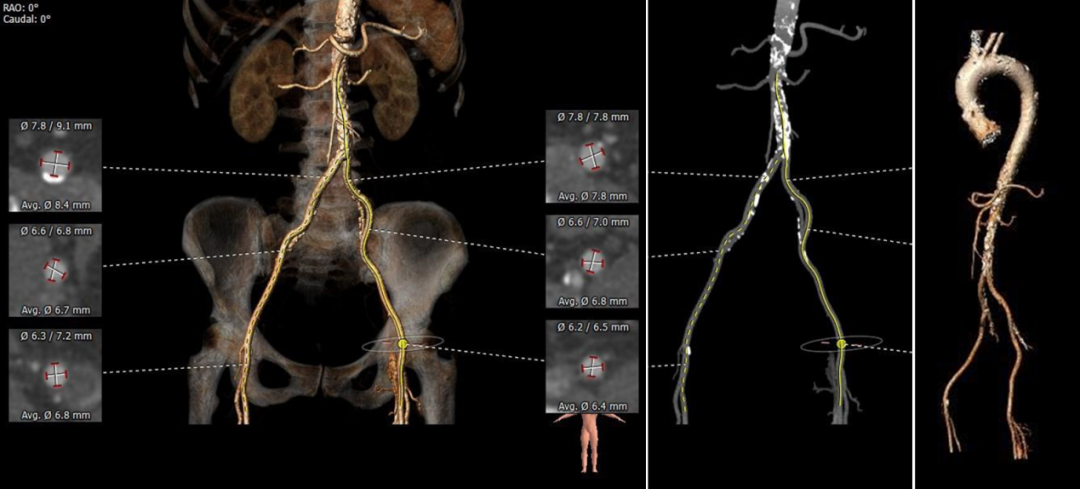

患者为71岁女性,影像学检查提示三叶式主动脉瓣,瓣膜增厚钙化,开放重度受限,钙化积分HU850:722mm³,主动脉瓣口面积仅为0.7 cm²,平均跨瓣压差53 mmHg,主动脉瓣口峰值流速高达4.6 m/s,诊断为主动脉重度狭窄。葛均波院士亲自携多学科团队进行评估并制定了详细的手术方案,拟采用20 mm球囊进行预扩,植入AV26TaurusNXT主动脉瓣。术中通过多次使用回收功能寻找最理想的锚定位置和释放位点,并使用22mm 球囊进行后扩张。术后即刻经食道超声心动图评估显示仅微量瓣周漏,平均跨瓣压差仅为7 mmHg,主动脉瓣口峰值流速为1.9 m/s,术后即刻瓣口面积为2.0cm²,血流动力学指标理想。

主动脉根部及冠脉解剖分析:

血管外周入路评估: